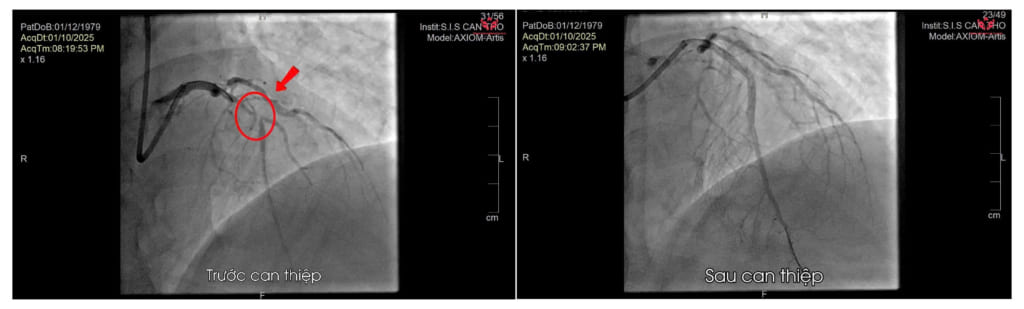

Kết quả chụp mạch vành cấp cứu ghi nhận tắc đoạn gần nhánh liên thất trước. Hình ảnh trước – sau can thiệp

Ê-kíp tim mạch khẩn trương hội chẩn và chỉ định chụp mạch vành cấp cứu, phát hiện tổn thương hẹp rất nặng ở đoạn gần nhánh liên thất trước. Bệnh nhân được đặt stent mạch vành cấp cứu để tái thông dòng máu.